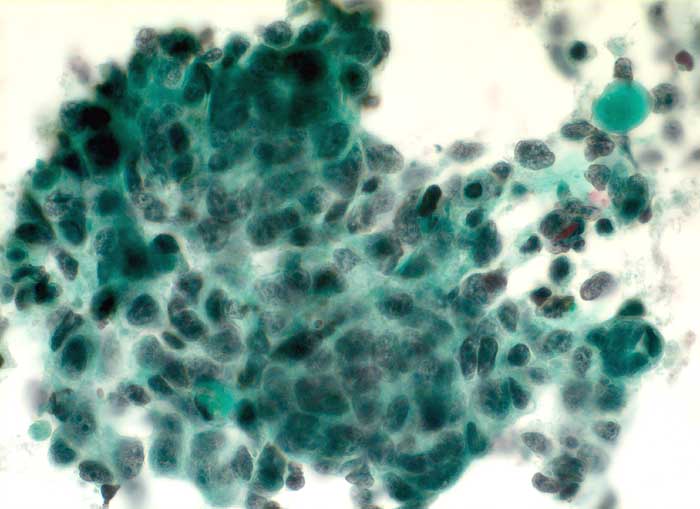

Einleitung

Unten finden Sie Beispiele von Metastasen eines Plattenepithelkarzinoms, eines Adenokarzinoms und eines kleinzelligen Karzinoms.